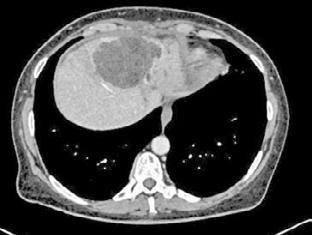

Durante las primeras horas de ingreso, mala evolución clínica y elevación de biomarcadores con procalcitonina 18ng/dL y proteína C reactiva de >350mg/dl por lo que se realiza angio-TC abdominal dónde se observa pancreatitis aguda edematosa con trombosis parcial de la vena esplénica sin otras complicaciones asociadas.

Situación muy condicionada por hipertensión intrabdominal y situación de íleo paralítico. Presión intraabdominal (PIA) inicialmente superior a 22 cmH20. Se inician procinéticos de forma precoz junto con enemas puntuales con los que se consigue resolver la situación de íleo y disminución progresiva de la PIA con mejoría clara de la exploración abdominal.

gánico. El paciente presentaba una hipertensión intraabdominal grado II-III, con una presión intrabdominal (PIA) persistentemente elevada (>20 mmHg) y un fallo multiorgánico asociado. En este caso se presenta una situación de insuficiencia respiratoria aguda, vinculada a un SDRA grave, y un síndrome compartimental abdominal.

Cortes axial y coronal de TC toracoabdominal en la fase inicial (A y B) y la evolución posterior (C y D). Se puede apreciar la evolución de pancreatitis edematosa (A) a pancreatitis coleccionada (D). A nivel torácico destaca signos de restricción abdominal (B) precoces en probable contexto de hipertensión intraabdominal elevada, con posterior evolución a atelectasia de zonas declives y afectación parenquimatosa heterogénea (D).